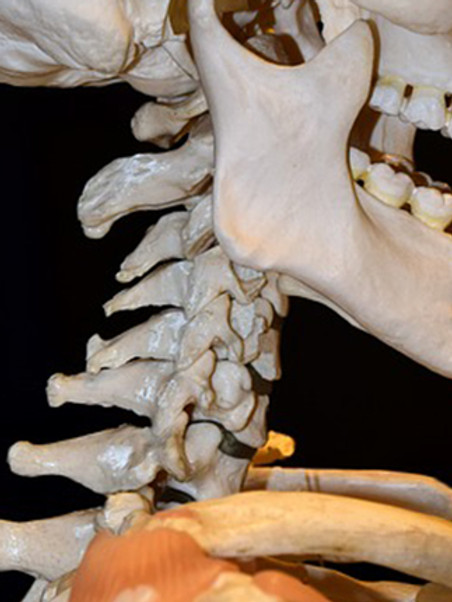

목디스크란 목뼈 사이에 있는 디스크가 손상되어 신경을 압박하는 질환을 의미합니다. 디스크는 젤리와 같은 수핵과 섬유륜으로 구성되어 있습니다. 섬유륜이 손상되면 수핵이 밖으로 밀려나와 신경을 압박하게 됩니다.